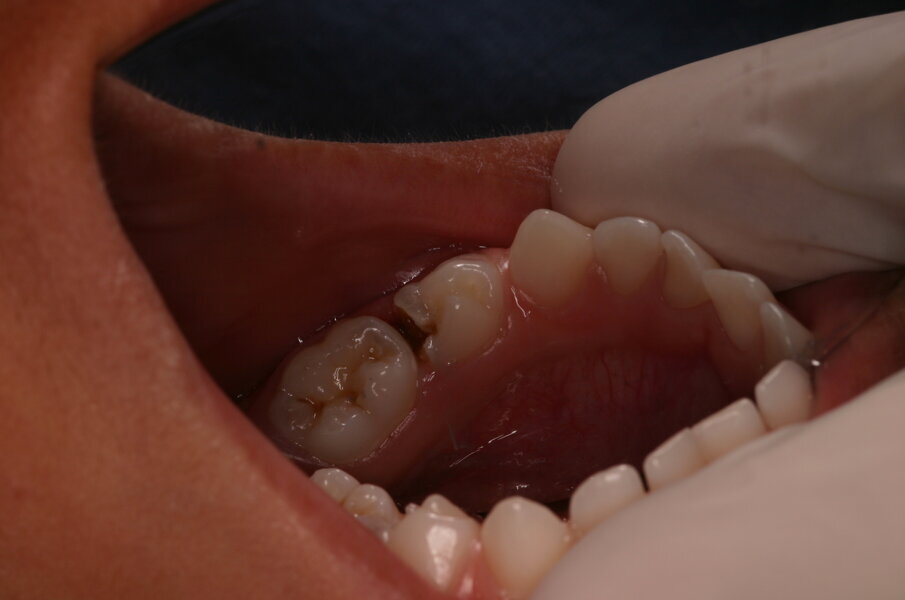

Tandenpoetsen doen veel mensen, ook al verschilt de mate van grondigheid ervan. Weinig suiker gebruiken is veel lastiger. Immers mensen moeten iets lekkers achterwege laten en dat is moeilijk. Het is belangrijk om goede hoofdmaaltijden te gebruiken om niet te hoeven snoepen voor energie. Wil je dit bereiken dan is verwijzing naar een diëtist misschien wel de geëigende weg. Daarom is het altijd belangrijk om het grondig reinigen van tandoppervlakken te benadrukken in het voorkomen van tandcariës. In veel gevallen lukt het ouders en kind(eren) om tanden en kiezen gaaf te houden. Bij anderen is dat moeilijker. Dentinecaviteiten ontstaan en de aanjager ervan moet beteugeld worden. Die aanjager is cariogene plaque. In een caviteit is die plaque op de bodem en aan de wanden te vinden. Om dezelfde reden als voor het gezond houden van gave tandoppervlakken moet plaque uit de caviteit verwijderd worden. De meest voor de hand liggende manier om dat te bereiken is door het schoonpoetsen met tandenborstel en fluoridehoudende tandpasta. Echter, de caviteit moet dan wel toegankelijk zijn. Het is duidelijk dat de toegankelijkheid in kleine caviteiten moeilijk tot onmogelijk is. Grote caviteiten kunnen gemakkelijk worden bereikt en middelgrote caviteiten kunnen vergroot worden. Dat laatste kan gebeuren met een diamantfineerboortje (afbeelding 1) of met een glazuurmes (afbeelding 2). Door het glazuurmes te plaatsen op onondersteund glazuur fractureert dit glazuur onder geringe druk en wordt voldoende toegang gecreëerd (afbeelding 3a-b). Deze poetsbehandeling van cariës wordt causale behandeling genoemd.

- Schoonpoetsen met tandenborstel en fluoridehoudende tandpasta van toegankelijke caviteiten (afbeelding 4).

- Toegankelijk maken van middelgrote niet-toegangelijke caviteiten, behandelen volgens 1.

Kleine caviteiten kunnen gerestaureerd worden volgens de atraumatic restorative treatment (ART) (afbeelding 5a-c).